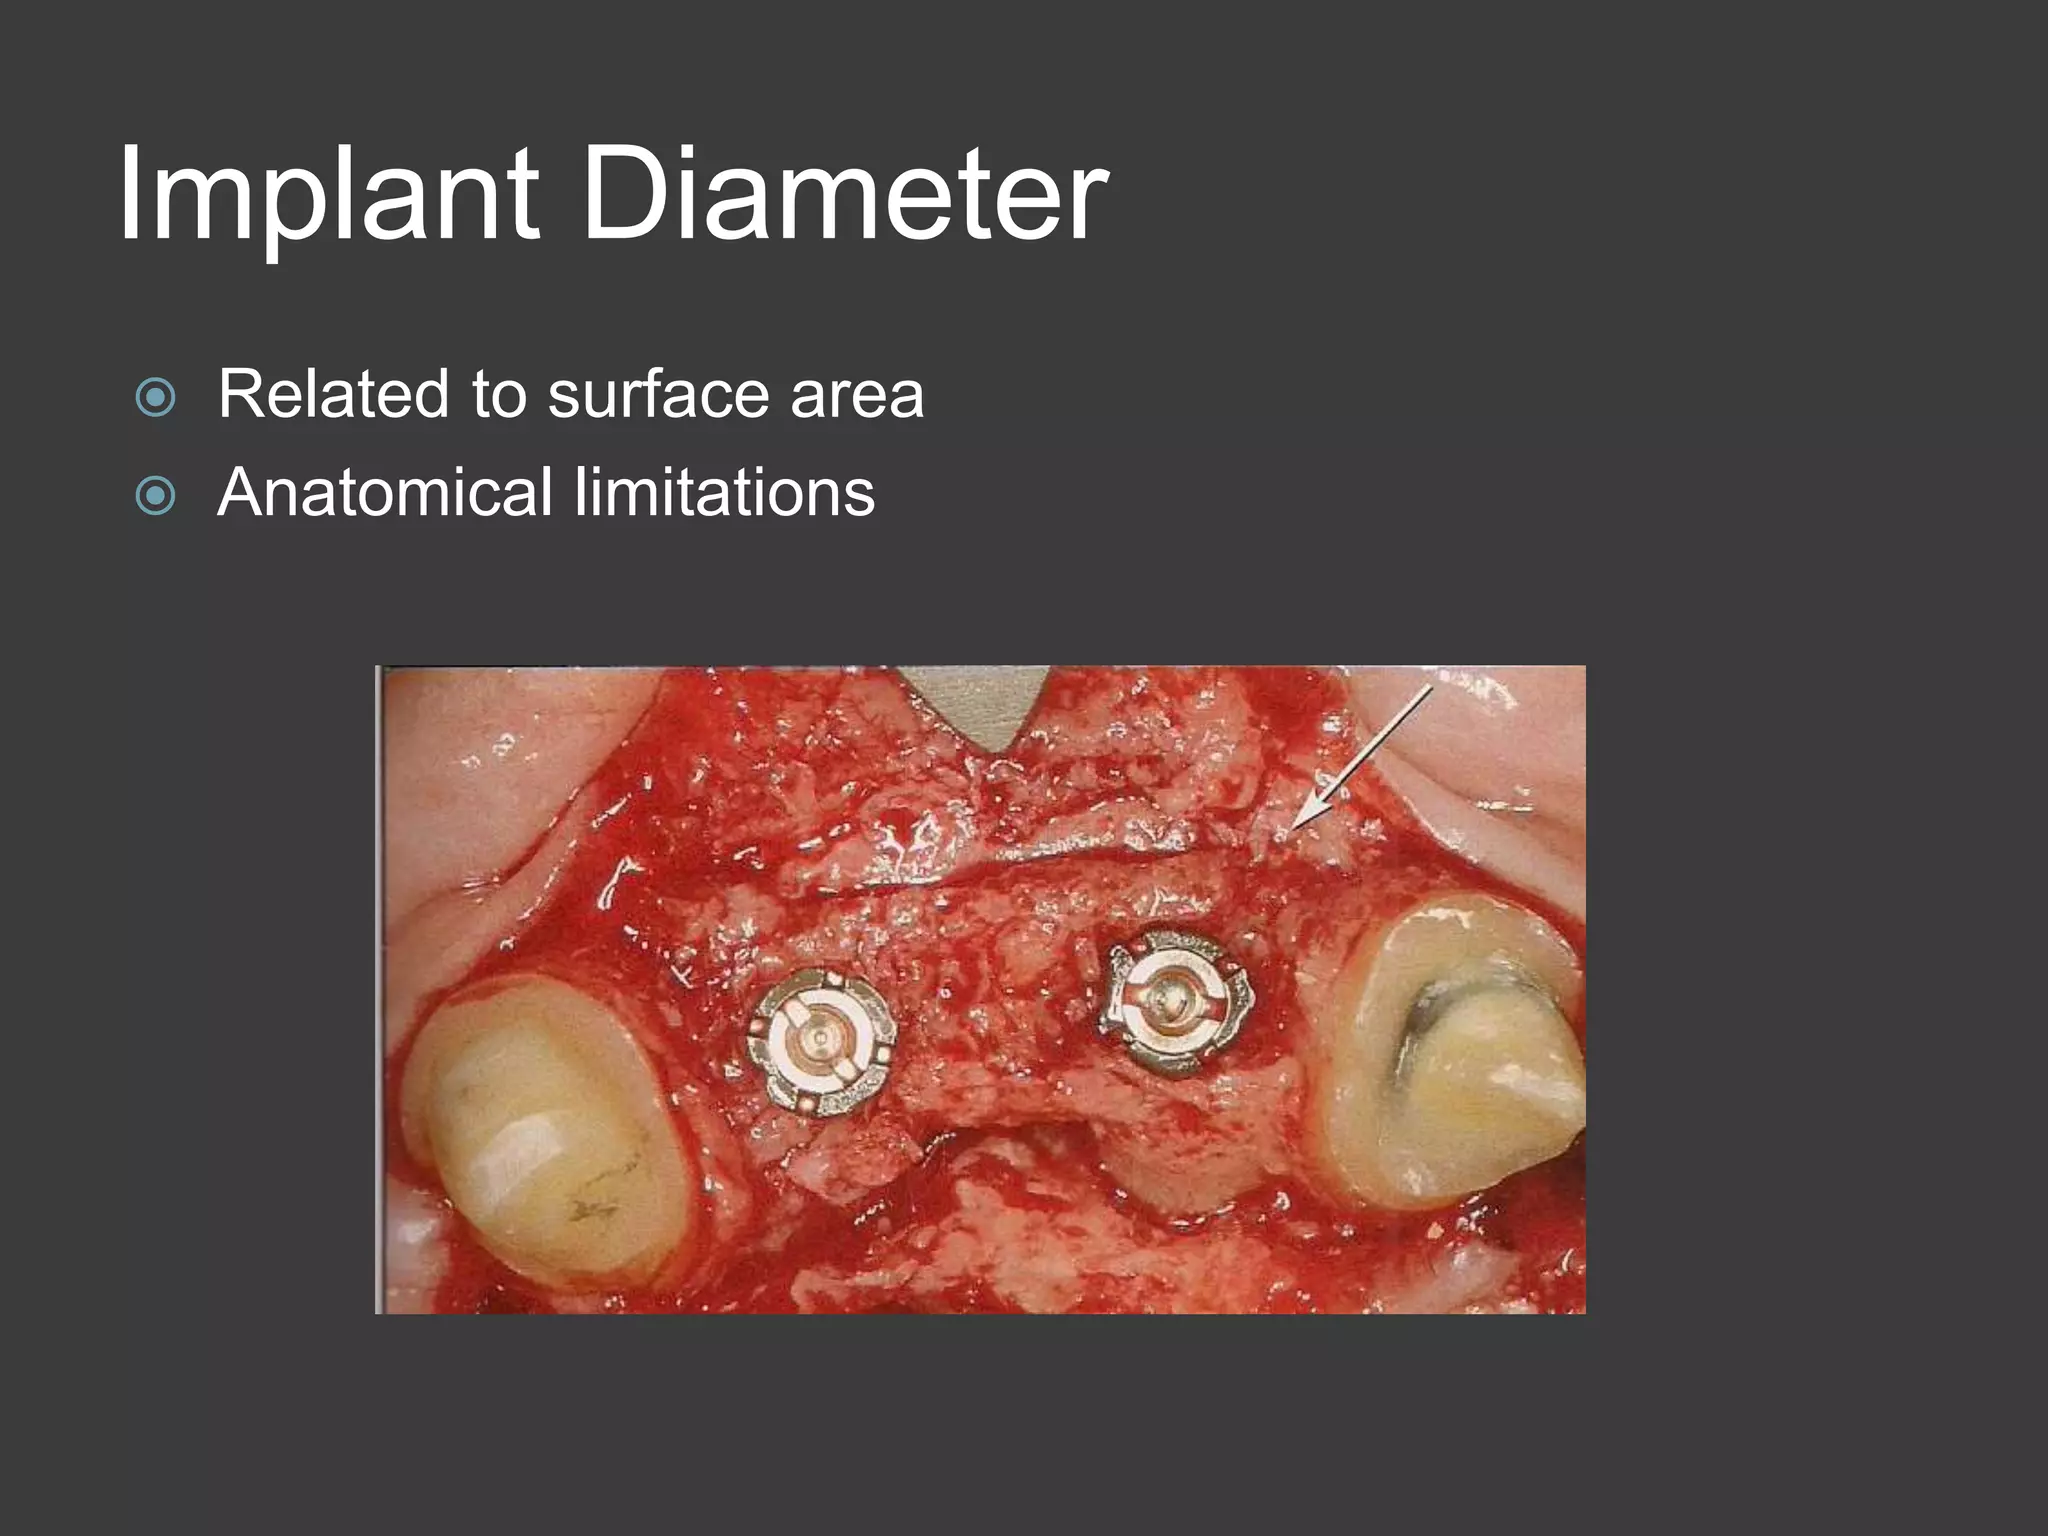

This document discusses factors that influence osseointegration and primary stability of dental implants, including implant design characteristics, surgical technique, and loading protocols. Specifically, it covers the processes of osseointegration and how forces on implants can either promote or inhibit bone remodeling. Key implant design considerations like length, diameter, threads, coatings and surface topography are analyzed in terms of their effects on stress distribution and bone-implant contact. The importance of primary stability and factors influencing it like bone quality and surgical skill are also addressed. Loading protocols ranging from immediate to conventional loading are compared.